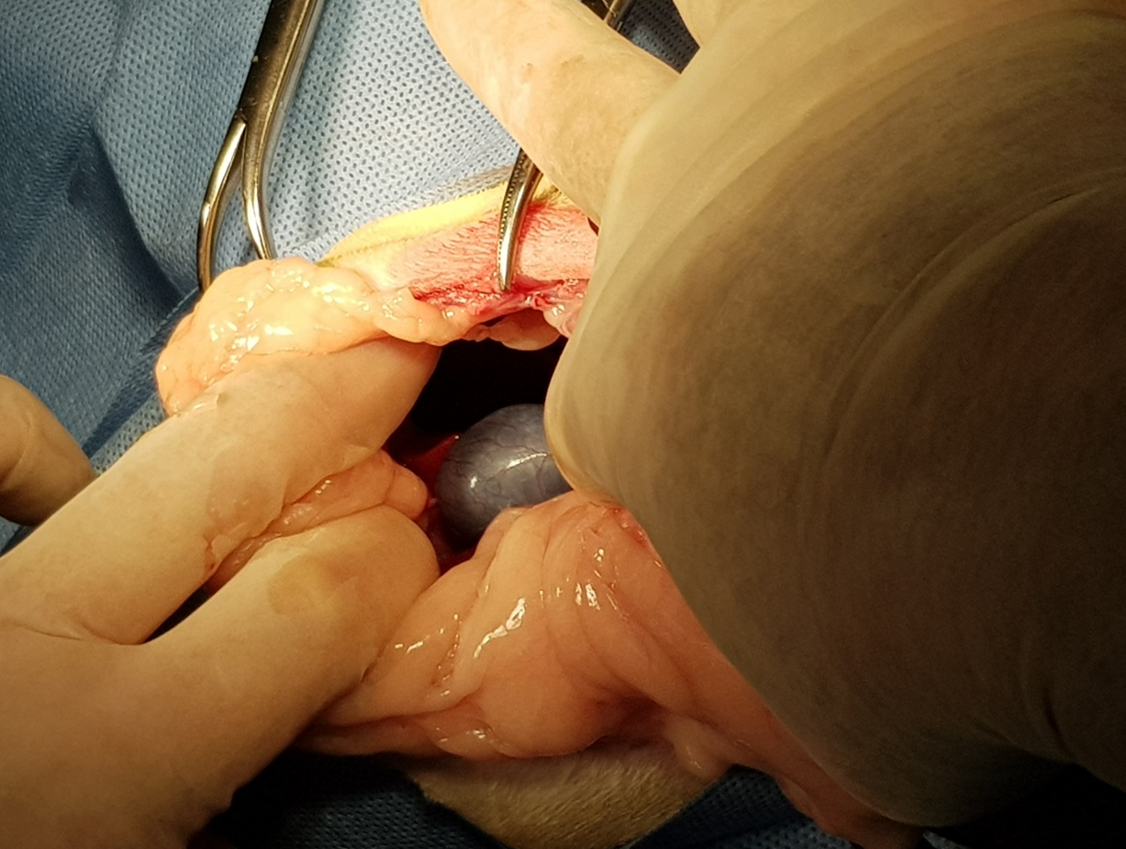

開腹後發現肝臟從腹腔掉到胸腔內,橫膈破了一個大洞

將橫膈修補起來,看到破洞縮小很多

看到橫膈膜全貌

將胸腔內的空氣抽掉讓肺臟可以正常的擴張